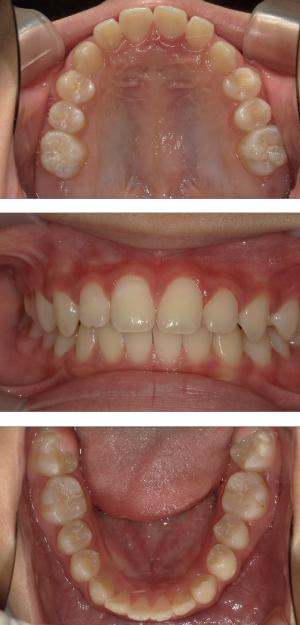

バイオブロック矯正(顎顔面口腔育成治療)

矯正治療は大人になって始めるよりも子どもの頃から始めた方が確実に良い結果をもたらします。成長が盛んな子供の時期に、顎や顔の成長を利用しながら治療ができる大きなメリットがあるからです。当院では、非抜歯矯正を推奨しておりバイオブロック矯正を取り入れています。

バイオブロック矯正の考え方は歯並びが悪くなる原因にアプローチする治療法になります。

舌の位置や口呼吸から乱れてしまった下顎の後退を正し、顎顔面が本来あるべき位置へと誘導させていく治療です。

- 歯並びの改善